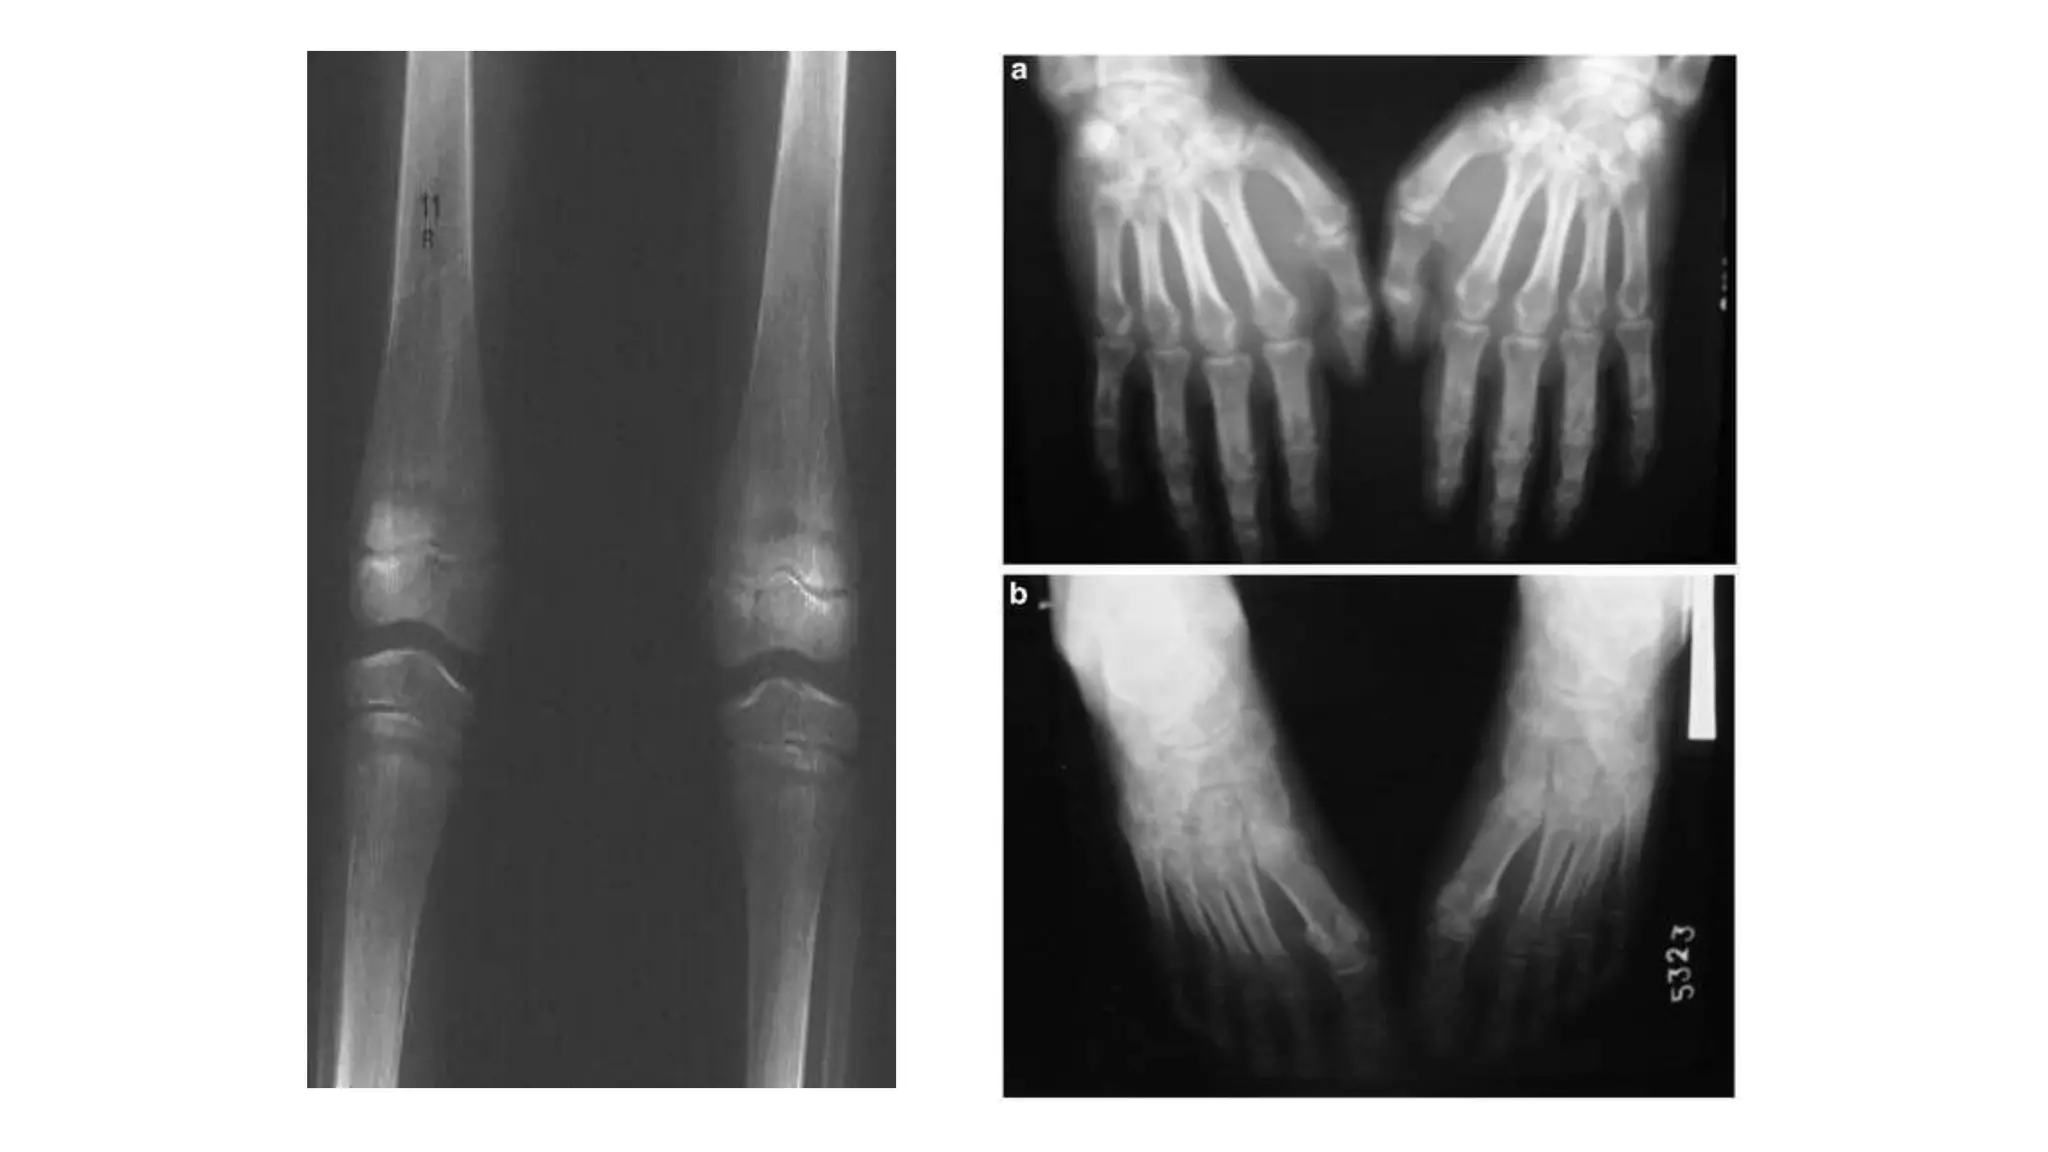

Four Informative Skeletal Sites

1.Radius -The distal one-third of the radius (wrist) is

efficacious in predicting fracture risk.

2.Phalanx-The proximal phalanx.

3.Metatarsus-The 5th metatarsus.Measurement at this

site is particularly important because weight-bearing

bone may lose strength at a different rate than non-

weight-bearing bone.

4.Tibia-The mid-shaft of the tibia.It is useful in the

monitoring of treatment for osteoporosis.

• The diagnosis of osteoporosis can be made by using

conventional radiography and by measuring the BMD using

DEXA which is the gold standard for diagnosis.

• The main radiographic features of generalized

osteoporosis are cortical thinning and increased

radiolucency.

Four Informative SkeletalSites 1.Radius -The distal one-third of the radius (wrist) is efficacious in predicting fracture risk. 2.Phalanx-The proximal phalanx. 3.Metatarsus-The 5th metatarsus.Measurement at this site is particularly important because weight-bearing bone may lose strength at a different rate than non- weight-bearing bone. 4.Tibia-The mid-shaft of the tibia.It is useful in the monitoring of treatment for osteoporosis.